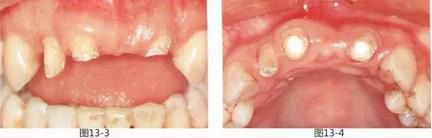

圖13-8  術后正面照。

圖13-9  術后咬合面照。